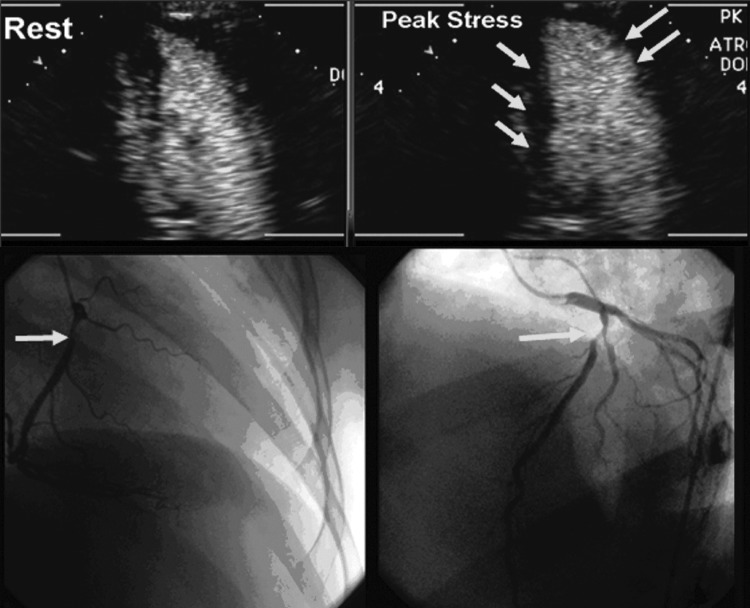

Cardiac CT for coronary calcium was performed in 124 (33.9%) women, mean CAC score 39.7±84.0 (range 0–431), excluding a single patient with an outlier value of 1026; 107 (86%) women had a CAC score ≤100, whereas in 17 (14%), it was >100. CAC was localized to the LAD in 51 (13.9%), right coronary artery (RCA) in 23 (6.3%), and circumflex artery (CX) in 18 (4.9%); 65 women (52.4%) had a CAC score of zero. CSE was abnormal in 14 (11.3%), and CAC was present in 6 (42.9%), while 110 women had normal CSE, and CAC was present in 53 (48.2%). Mean CAC score was not different in women with abnormal vs. normal CSE (37.29±74.28 vs. 48.44±126.98, p=0.636). When stratified according to CAC score categories (≤100 or >100), the majority of women in each group had normal CSE (Fig. 2B). There was no correlation between CAC score and peak stress WMSI (r=0.149, p=0.098). Figure 3 shows multimodality imaging results in a 43-year-old woman with inducible ischemia in the distribution of RCA on dobutamine-CSE, positive stress ECG (1–1.4 mm horizontal inferior ST segment depression), multivessel CAD (90% RCA and 60% LAD stenoses) yet no detectable CAC on cardiac CT.

FIG. 3.

Representative imaging studies from a 43-year-old women with (Top) rest and of stress views inducible ischemia in RCA and LAD distribution on dobutamine-CSE (arrows, lack of inward motion of inferior and anterior walls at end-systole compared to rest image) with positive stress ECG (1–1.4 mm horizontal S-T depression) in inferior leads, yet no detectable CAC. (Bottom) Coronary angiography: 90% proximal RCA and 60% proximal LAD stenoses (arrows).